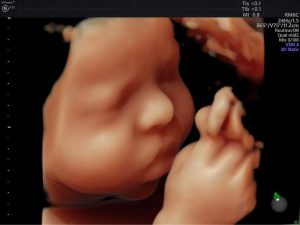

Ngày nay, với sự phát triển của công nghệ y học cho phép mẹ nhìn ...

Siêu âm 3D sẽ giúp chúng ta nhận được những hình ảnh tương đối rõ ...